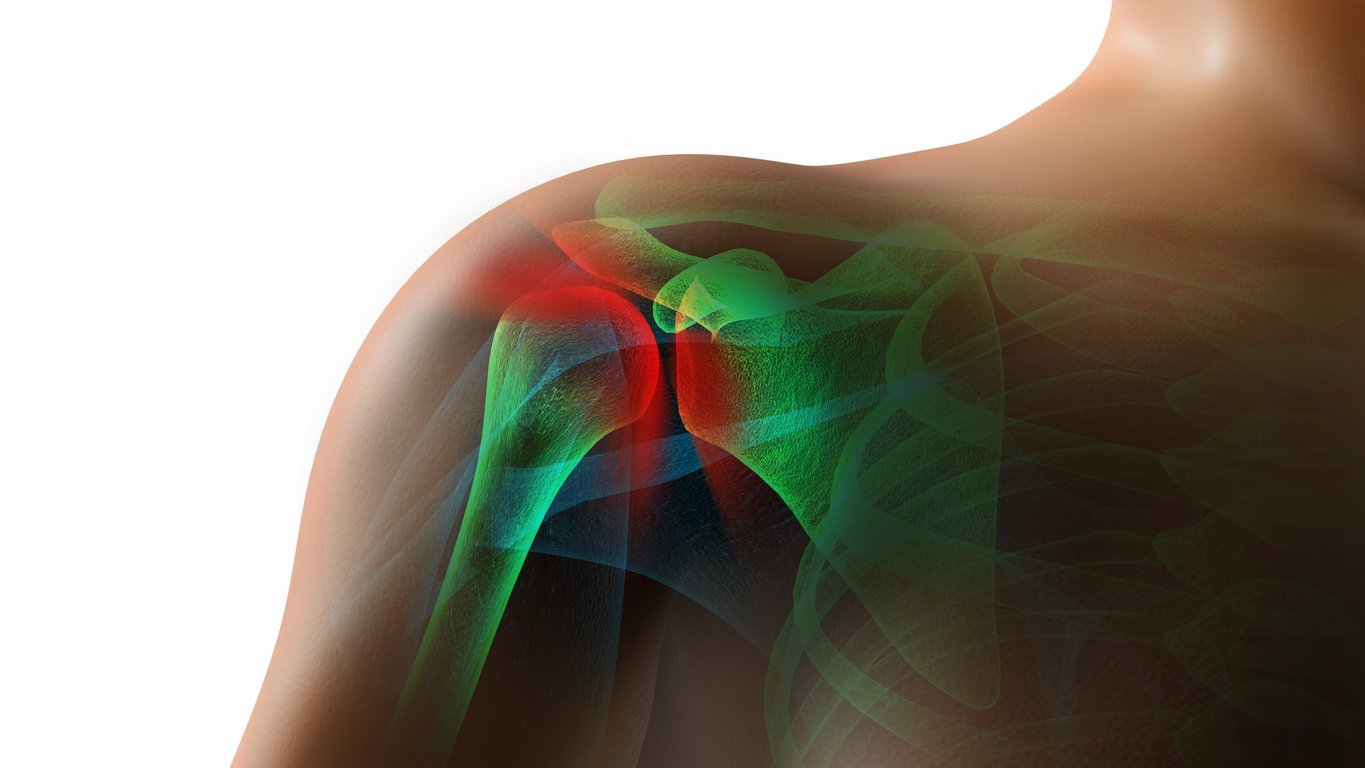

Shoulder Pain

The shoulder is a unique joint and is one of the most frequently injured joints of the body. A reason for this is that the shoulder is the most mobile joint in the body. The shoulder has three planes of motion to provide a high level of function.

This high degree of mobility creates a larger potential for the development of shoulder pain and injury.

Shoulder Anatomy

Shoulder Pain

Shoulder Pain

Shoulder Pain